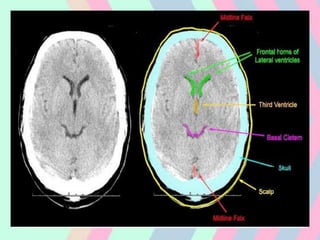

CT SCAN

• Revolutionized diagnostic neuroradiology by

permitting imaging of the brain tissue in live

patients.

• The first CT Scanner was developed in 1972

by Godfrey Housenfield of UK.

• The amount of radiation that passes

through, or is not absorbed from, each angle

is digitized and entered into a computer.

• The computer uses matrix algebra

calculations to assign a specific density to

each point within the head and displays these

data as a set of two-dimensional images.

When viewed in sequence, the images allow

mental reconstruction of the shape of the

brain.

• CT images determined only by degree to

which tissues absorb X-ray

• Bone, clotted blood, calcified tissue,

contrast material appear white & CSF black.

• The only component of brain better seen on

CT scan is Calcification, which may be

invisible on MRI.